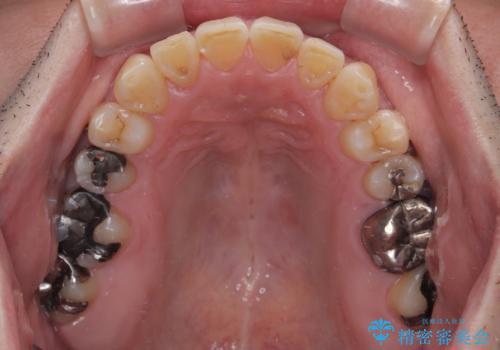

むし歯をきっかけに矯正治療を行うこととなりましたが、学生の頃から気になっていた歯列を改善することができ、患者様には大変満足していただけました。